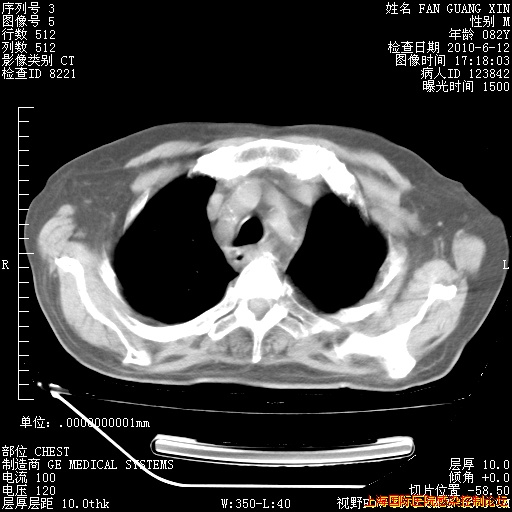

6月12日纵膈窗